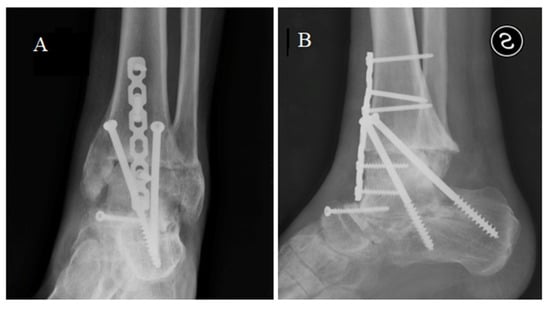

We proposed a tibial resurfacing, but the patient preferred a triple arthrodesis. Via anterior-medial access, the prosthesis was removed, and a fusion of the ankle, subtalar, and talo-navicular joint was performed with the use of a bone graft (Figure 6). At the last follow-up, 5 years after surgery, the patient was pain-free, wore normal shoes, and walked with a very slight limp. The AOFAS score was 81.

Figure 6.

X-ray in anterior posterior (A) and latero-lateral (B) projections showing the tibio-calcaneal arthrodesis.